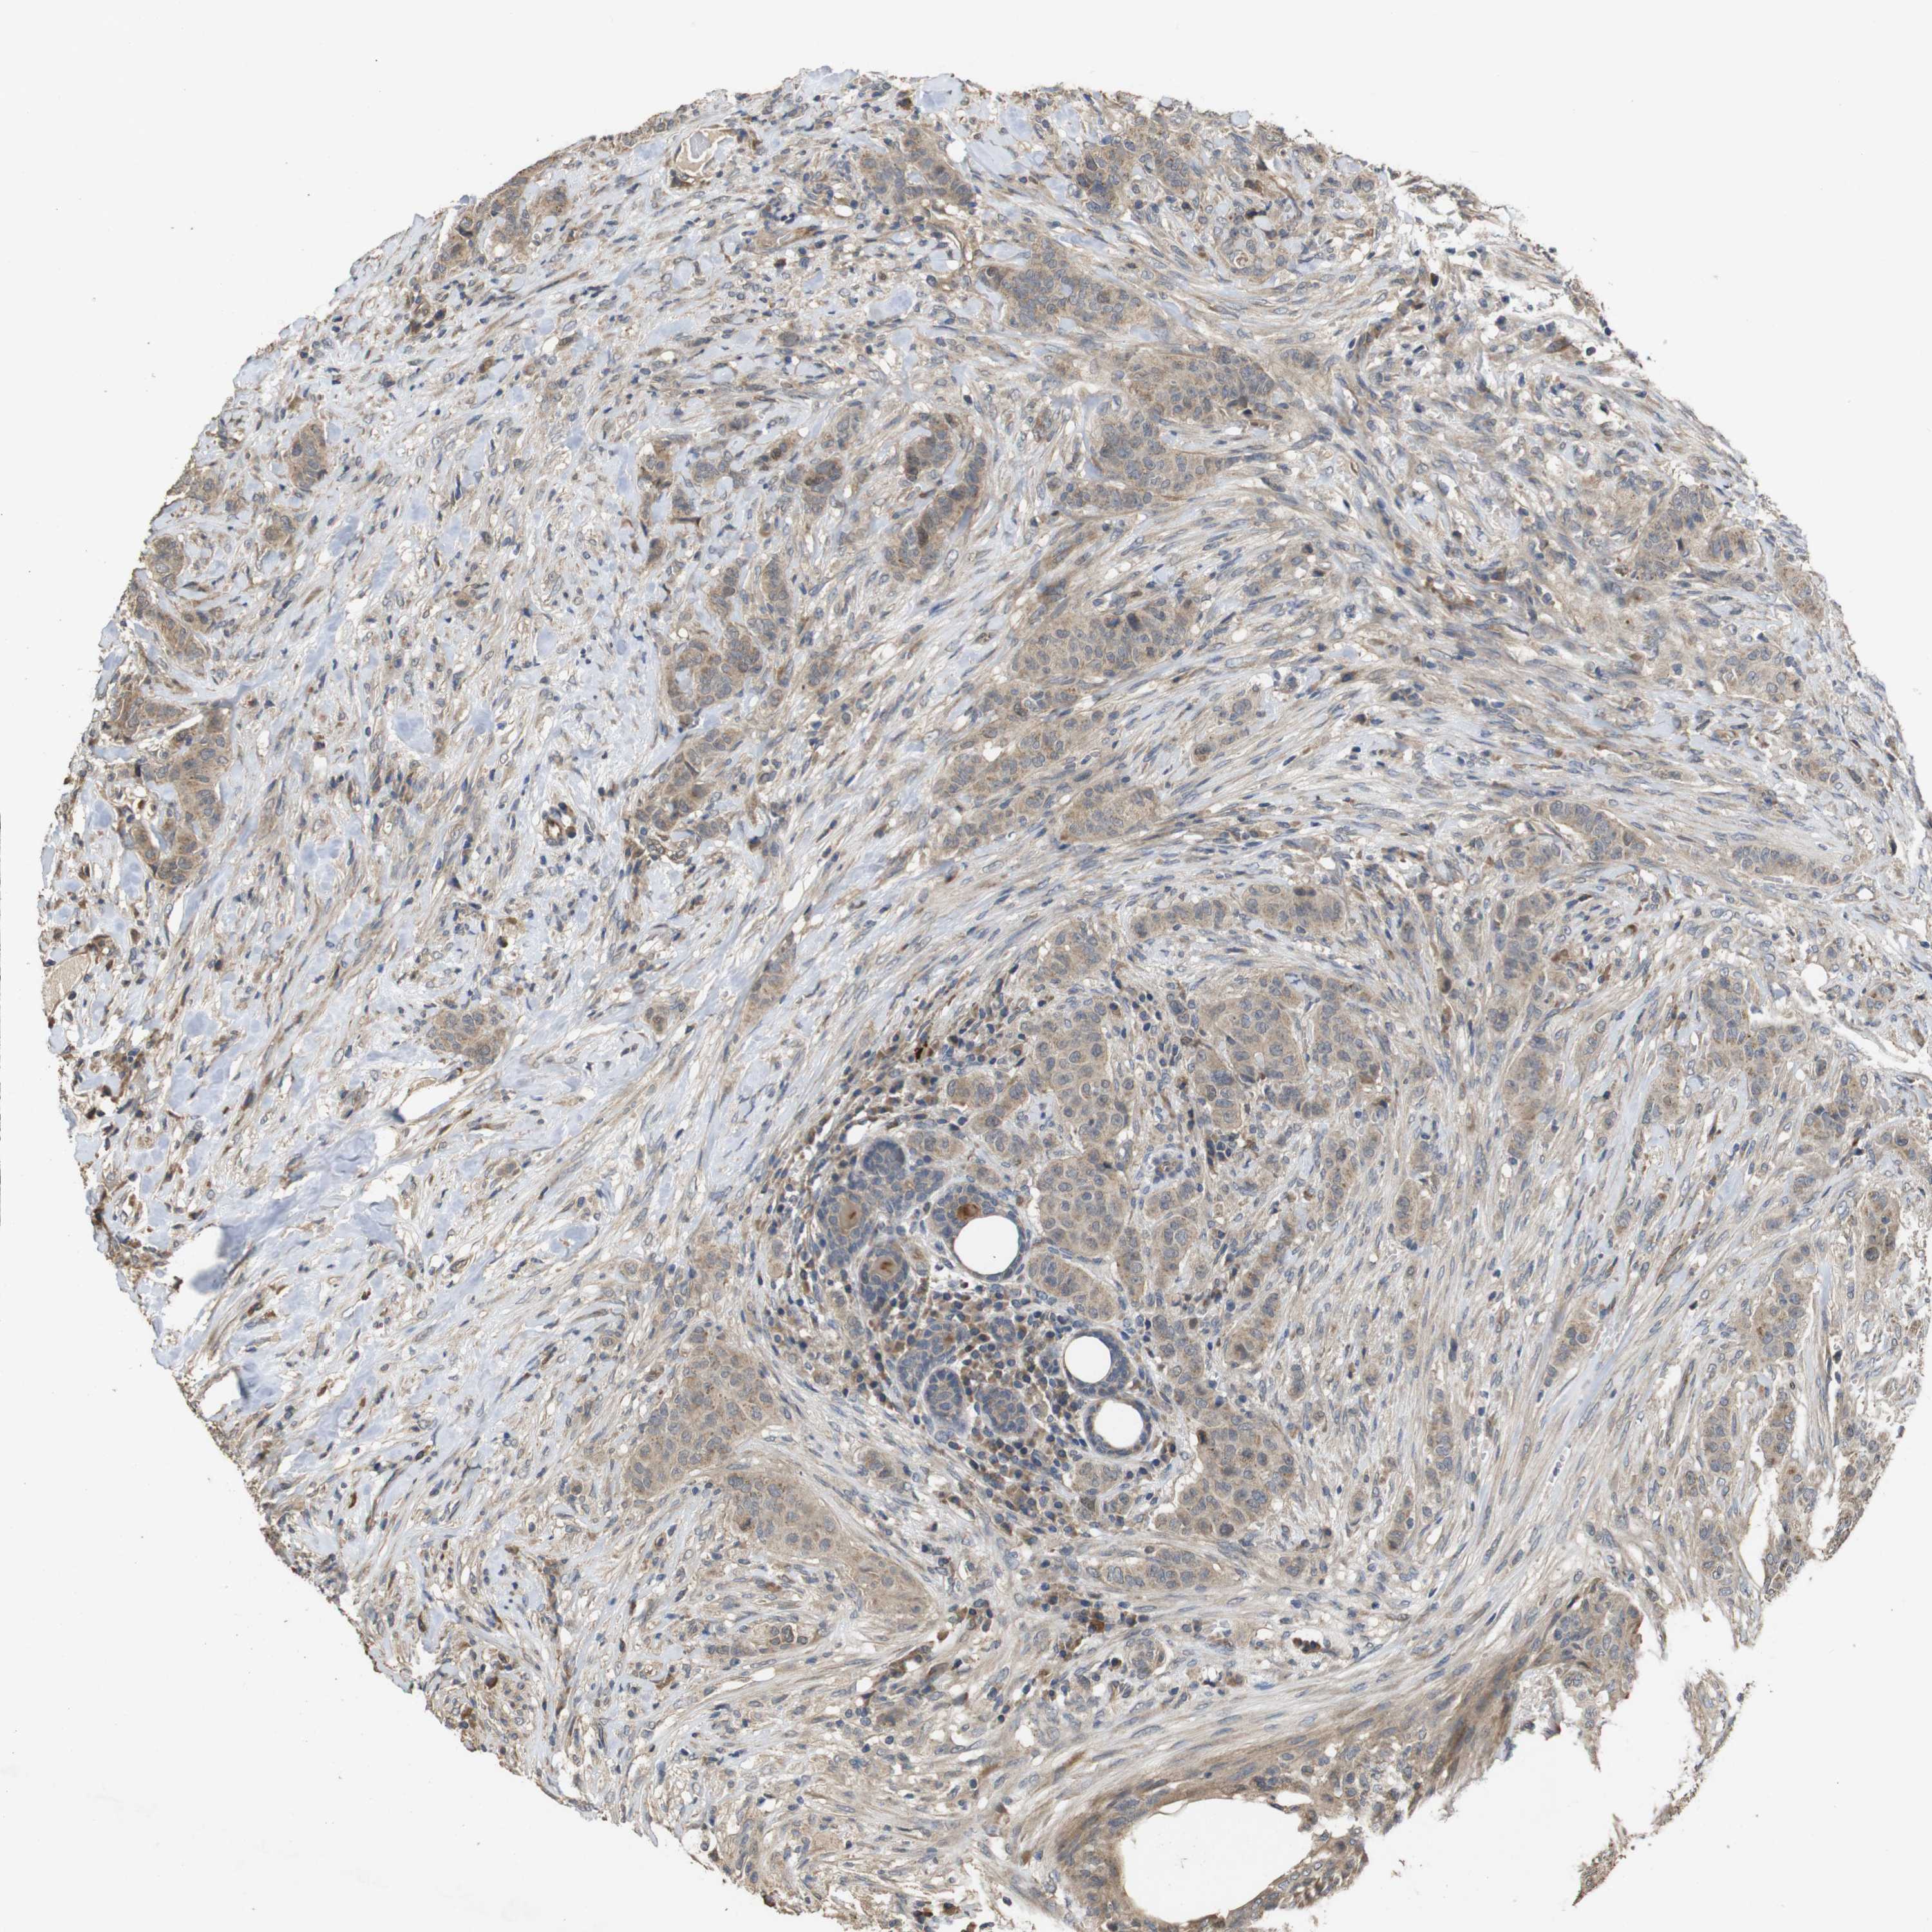

BRCA TCGA BRCA VALIDATION PROTEIN EXPRESSION

ANTIBODIES

AND

VALIDATION